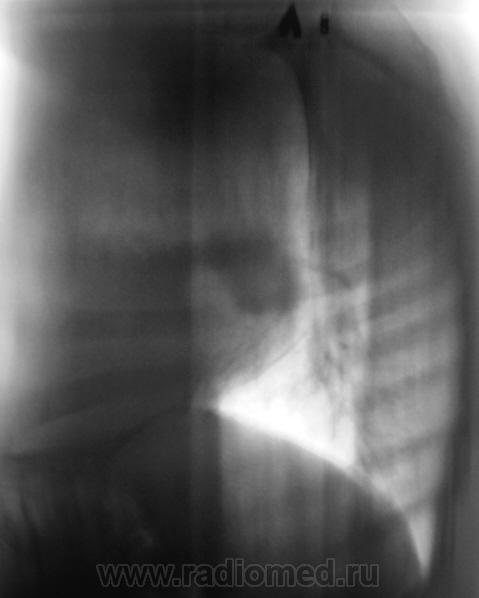

1. Прежде всего, я побеседовал с гражданином и "выяснил", что ему сказали и "посоветовали" в высоком специализированном лечебном учреждении.

2. Конечно, мы на свой страх и риск, произвели дообследование, согласно стандарту. Итог дообследования представлен в серии 3.

Все признаки периферического рака...."расти" так может и лет пять...пока репу в диспансере будут чесать...

В заключении, именно однозначно, выставлен данный диагноз, изображения и все необходимое записано на диск. Это не ошибка для ООД. В ООД такой ошибки быть не может, ибо это специализированное учреждение.  Кстати, это, как Вы понимаете, случай не единичный.